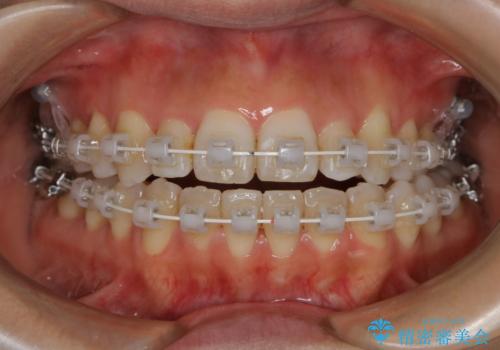

非抜歯、ワイヤーでの矯正治療。歯のがたつき、顎のズレ、出っ歯を治す。インビザラインが使えない方

- ワイヤー矯正 審美装置

- 歯のガタつき、顎のズレ、出っ歯を気にして来院された患者様です。

歯を抜きたくないとの希望であったためマウスピース治療をお勧めしましたが、

マウスピースをずっとつけていることは難しいとの事であったためワイヤー矯正治療を行うこととなりました。

インビザラインの方法でも治せる患者様でしたが、希望によりワイヤー矯正となりました。